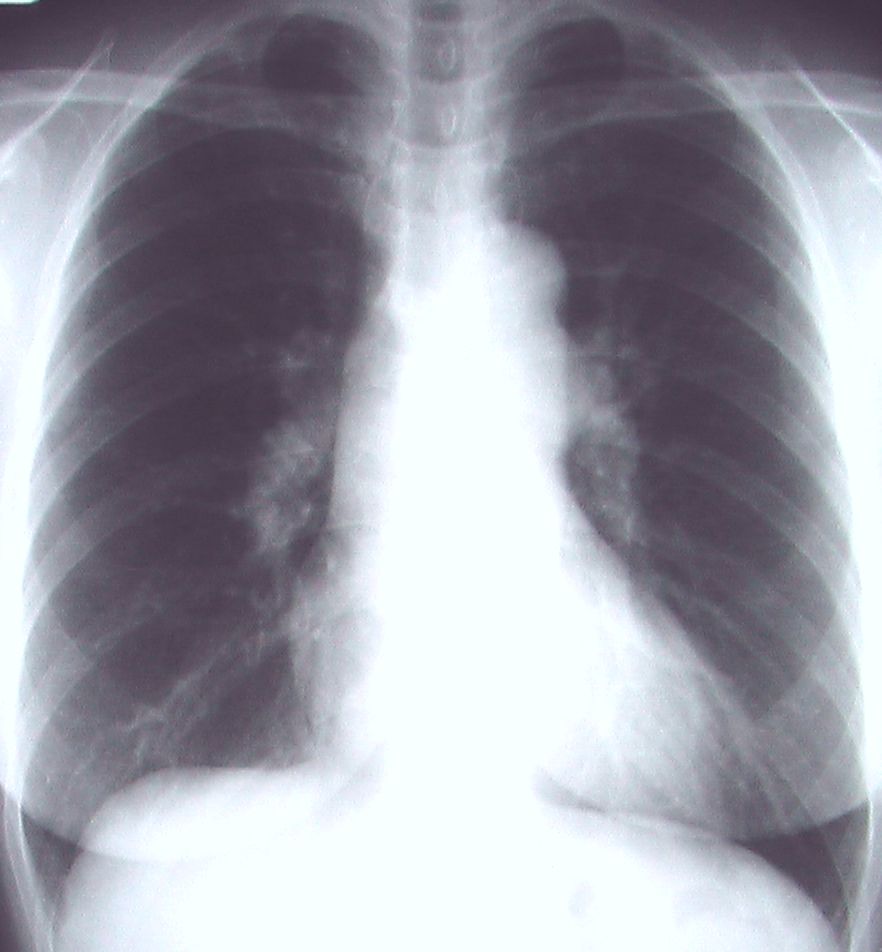

縦隔の拡大があり内部をみると血管陰影もしくは左房陰影の可能性があるが、右縁は大動脈弓に連続しており大動脈の蛇行(上行・胸部)と考えられる(横型心陰影にみられる正常バリエ-ション)右S3の結節影と縦隔の下部の不鮮明な所見には注意。